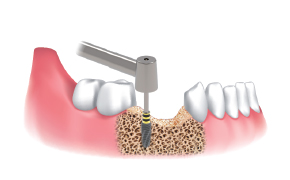

After the implant placement, healing abutments were connected and carried out GBR in the defected area.

* 2 Step Harvesting : Drilling to 7mm is recommended after transferring bone chips to bowl since the Stopper & Silicone Shield are fully filled with bone chips while 4mm drilling.